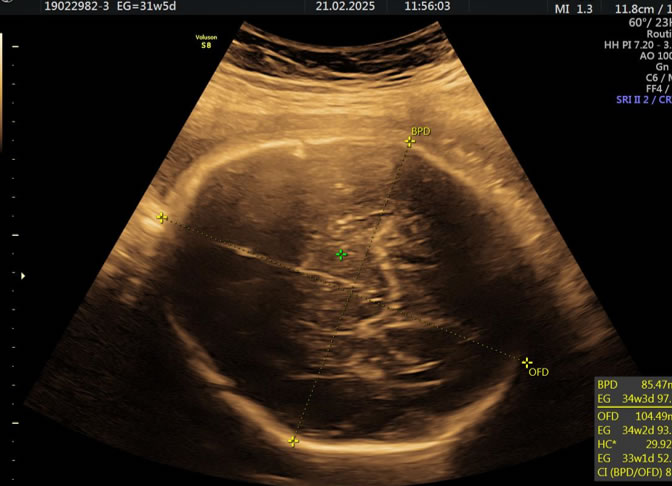

• Eco Doppler III Trimestre